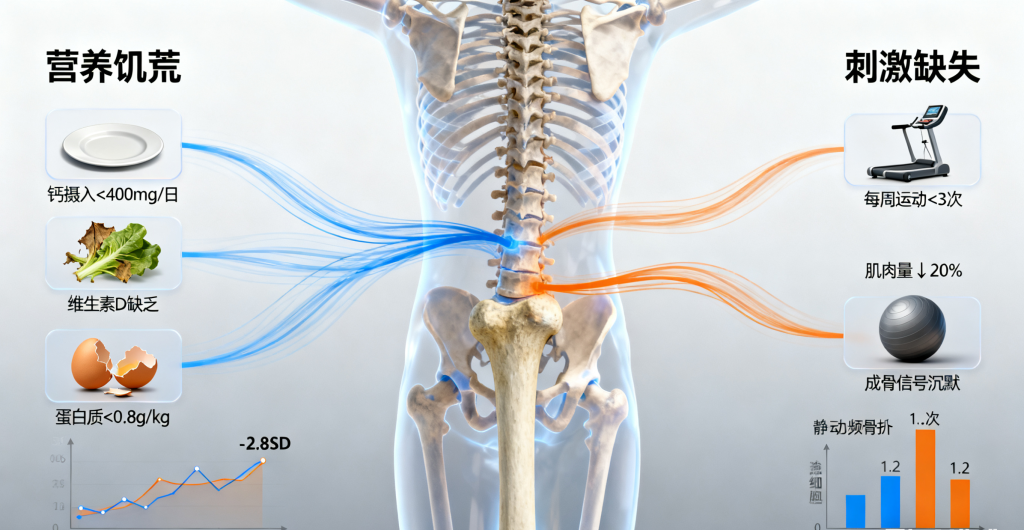

低体重人群的骨骼如同缺乏养护的危房,面临双重打击:·